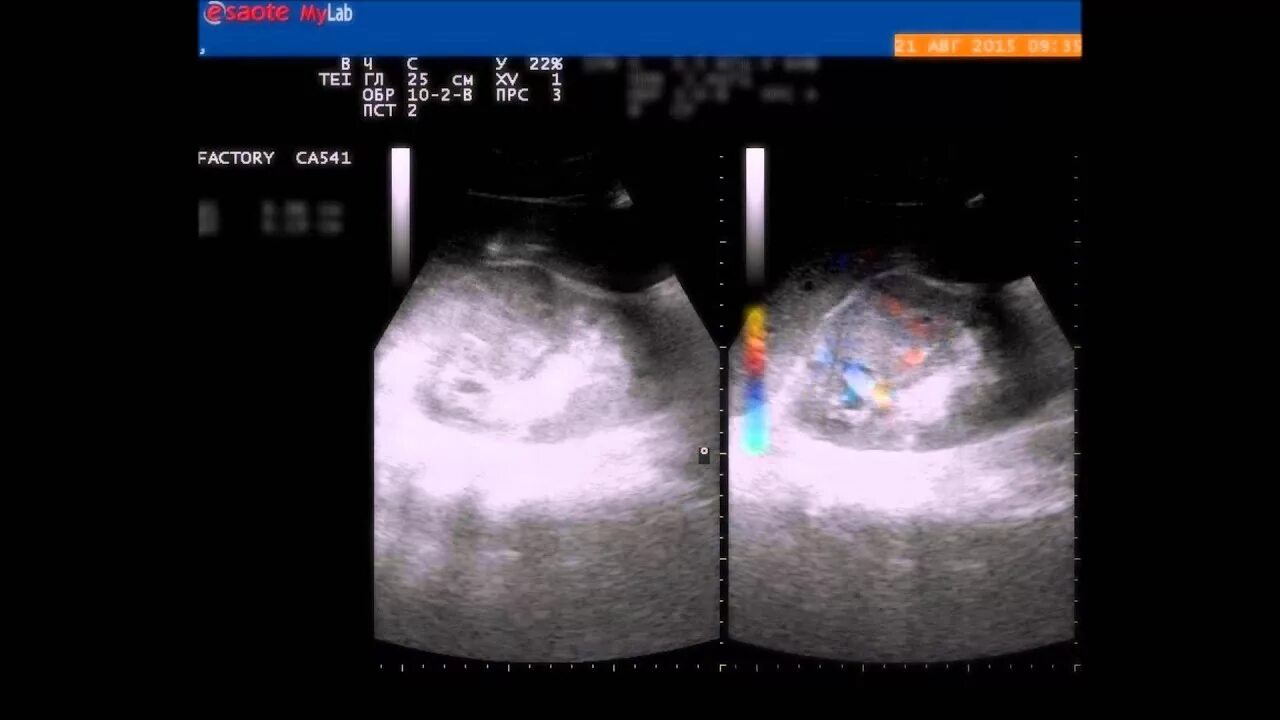

Прогноз рака почки с метастазами